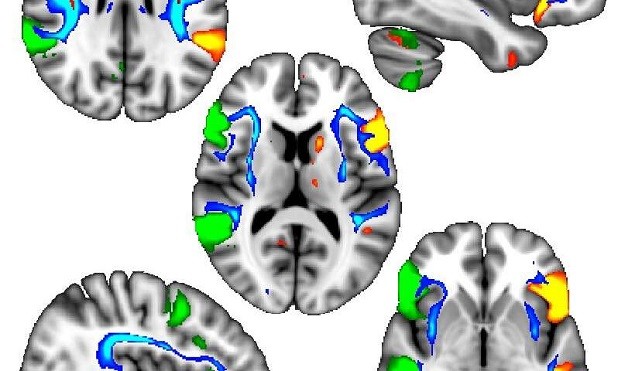

محققان با استفاده از تصویربرداری دقیق از حدود ۱۰۰۰۰ نفر از این شرکت کنندگان، دریافتند که این اثرات ژنتیکی با تفاوت در ساختار مغز در راههای عصبی ماده سفید همراه است که شامل اسکلت سلولهای مغزی است که مناطق مرتبط با زبان را به هم می پیوندند.

ما متوجه شدیم که در شرکت کنندگان چپ دست، مناطق زبانی سمت چپ و راست مغز با روشی هماهنگ تر با هم ارتباط برقرار می کنند. این احتمال جالب برای تحقیقات آینده را ایجاد می کند که چپ دستان هنگام انجام وظایف کلامی میتوانند از مزایایی برخوردار باشند. اما باید به خاطر داشت که این اختلافات فقط به عنوان میانگین در تعداد بسیار زیادی از مردم دیده می شود و همه چپ دست ها مشابه یکدیگر نیستند.

برای اولین بار در انسان، ما توانسته ایم ثابت کنیم که این تفاوتهای اسکلت سلولی مربوط به دست غالب واقعا در مغز قابل مشاهده است. ما از دیگر حیوانات مانند حلزون و قورباغه میدانیم که این اثرات ناشی از هدایت زود هنگام ژنتیکی است. بنابراین این احتمال غافلگیرانه را افزایش می دهد تا نشانه های اولیه تکوین مغز برای دست غالب در مرحله ی رحمی آغاز شود.